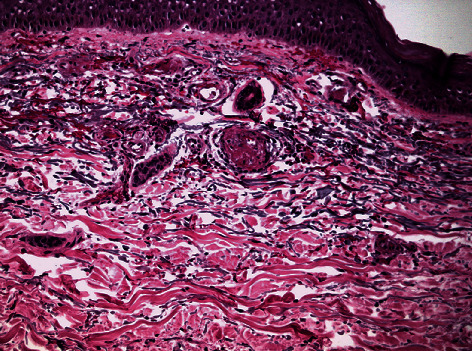

Histologic examination revealed the presence of occlusive vasculopathy of cutaneous microvessels, resembling disseminated intravascular coagulation, with minimal inflammation and no apparent vasculitis (Figure 2). Direct immunofluorescence showed the deposition of IgA, IgM, C1q, C3, C4, and fibrinogen on the endovascular fibrin clots. Transmission electron microscopy (TEM) was additionally performed on the same, formalin-fixed, paraffin-embedded biopsy block. Tissue cubes of 1 mm3 were cut with a razor blade and reprocessed, according to a protocol described by Graham and Orenstein [10]. After deparaffinization of skin biopsy blocks, small pieces of tissue were processed for conventional transmission electron microscopy. Specimens were fixed overnight in 2.5% glutaraldehyde, postfixed in osmium tetroxide, and embedded in epoxy resins. Thin sections were stained with uranyl acetate and lead citrate and subsequently observed with a Philips TEM 420 Electron Microscope. No viral inclusion structures were detected in the examined skin areas, including keratinocytes and endothelial cells (Figure 3). A SARS-CoV-2 specific RT-PCR was performed on skin samples, and the virus nucleic acid was not detected.

Endovascular fibrin clots. Generalized inflammation with a mainly perivascular pattern.

The present case report describes a critically ill, SARS-CoV-2 positive patient with cutaneous, purpuric/livedoid lesions that were biopsied. The histologic examination revealed the presence of small-vessel, thrombotic (resembling disseminated intravascular coagulation, DIC) vasculopathy with very limited inflammation and absence of vasculitis. Similar findings have been described in coagulopathies, idiopathic thrombocytopenic purpura, and systemic DIC due to infections. However, clinical and laboratory evaluation ruled out the diagnoses of these disorders. Specifically, the patient scored less than 5 at the International Society for Thrombosis and Haemostasis diagnostic scoring system for DIC, thus, precluding the diagnosis of overt DIC [14]. Drug-related reactions were also included in the differential diagnosis. Although there are reports that link hydroxychloroquine to variable cutaneous adverse reactions such as erythema multiforme [15], morbilliform eruptions [16], and Steven's-Johnson syndrome [17], the majority of these have been described in patients with autoimmune underlying conditions, which were not present in our case. Additionally, hydroxychloroquine-related skin manifestations are usually noted after substantial cumulative doses (usually after a duration of treatment that exceeds 2-3 weeks) [18].

In a case series described by Magro et al., pulmonary and cutaneous histologies from patients with severe COVID-19 were investigated, and it was reported that the purpuric skin lesions were associated with a pauci-inflammatory thrombogenic vasculopathy. In addition, the authors report deposition of C5b-9 and C4d, in both grossly involved and normal-appearing skin [9]. The histologic examination performed in our patient revealed similar findings; direct immunofluorescence demonstrated marked (+++) deposition of IgM, C3, and fibrinogen on vascular walls. IgA, C1q, and C4 deposition (++) were also present. These findings point strongly towards an intense complement activation that could potentially lead to a thrombotic-type coagulopathy. Complement activation may play a key role in the pathogenic process of COVID-19 and could be responsible for severe pulmonary morbidity; however, many questions remain unanswered. As the pathophysiological behavior of the host in response to the virus is currently being studied, it is becoming increasingly clear that the comprehensive and exhaustive examinations of all systems (including skin) are crucial elements of patient management.